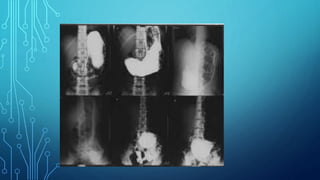

The special techniquesalso include a large group of X- ray contrast studies, in which the image is obtained using artificial contrast (bronchography, angiography, excretory urography, etc.).

Some organs areclearly visible in the images due to natural contrast (lungs, bones), others (stomach, intestines) are clearly visible on radiographs only after artificial contrast. Passing through the object of study, X- rays are delayed. Where the radiation is delayed more, shading areas are formed. Where there is less - enlightenment.